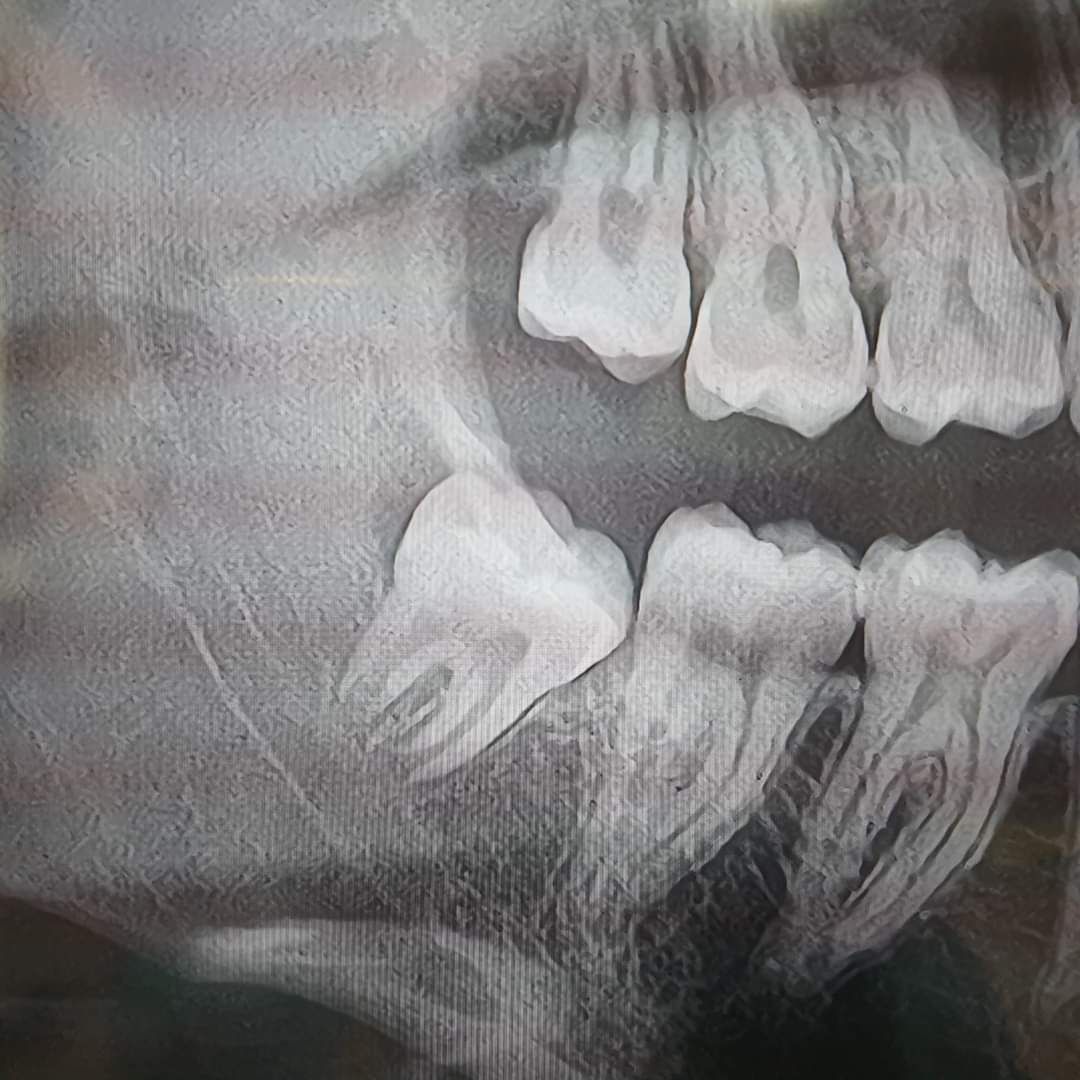

Ogni intervento di chirurgia orale inizia con una diagnosi accurata, grazie ad esami clinici e radiografici avanzati. Il nostro obiettivo è garantire procedure mirate che rispettino le esigenze di ogni paziente, alleviando il dolore e migliorando la qualità della loro vita. Contattaci per una consulenza personalizzata e scopri come possiamo aiutarti a ritrovare il benessere e la fiducia nel tuo sorriso!

L'estrazione dentale è una procedura comune nell'ambito della Chirurgia Orale, necessaria in diverse situazioni, come nel caso di un dente gravemente danneggiato, fratturato o con una posizione irregolare (disodontiasi) , tutte caratteristiche che influenzano la salute generale della bocca e, di conseguenza, il benessere del paziente. Presso il nostro studio, ci impegniamo a eseguire estrazioni dentali utilizzando tecniche avanzate e mirate, volte a preservare la massima quantità possibile di tessuto osseo circostante. Questo approccio è fondamentale in quanto consente una futura riabilitazione implantare, nel caso fosse necessaria la sostituzione dell’elemento dentale estratto. Ogni intervento viene realizzato seguendo rigorosi standard di sicurezza e comfort per i pazienti, garantendo un'esperienza il più serena possibile e minimizzando eventuali disagi. Ci teniamo a sottolineare l'importanza della comunicazione e della cura personalizzata, assicurandoci che ogni paziente si senta supportato e informato durante tutto il processo.